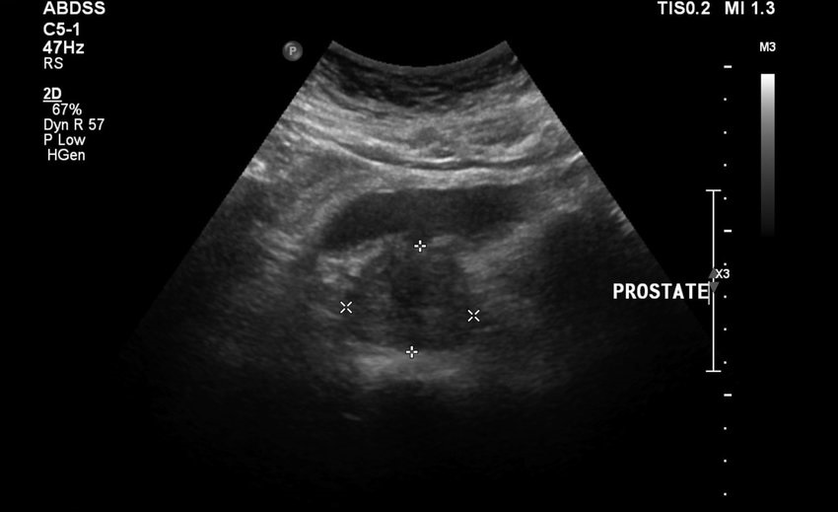

Nu au lăsat cauciucul să trăiască calm, apoi s -a adăugat durerile de spate inferioare, testele și rezultatele ecografiei au fost proaste. A fost literalmente imposibil să se îndepărteze de toaletă, a existat un sentiment de greutate în inghinal și dureri constante. S -a prescris masajul direct al prostatei, care m -a cufundat în panică. A început să caute alte metode de vindecare mai puțin traumatice.